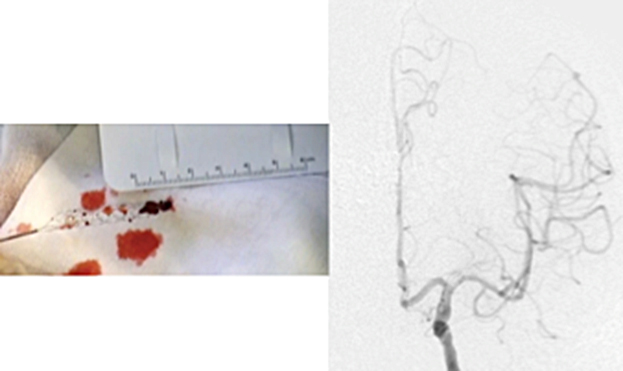

ステントは心筋梗塞や狭心症の時に細くなった心臓の血管を広げる時に使われているものとして知られております。ただ、血栓回収療法の時は少し違った使い方をします。血栓で詰まったところでステントを広げると、ステントが広がり血栓を押しつぶします。すると一時的に脳の血流が再開します。ただ、このまま様子をみるとステントの金網の中に血栓がめり込みます。そのうちめり込んだ血栓により再度血管が詰まってしまいます。これでは意味が無いのでは、と思ってしまいますが、再度詰まることでステントが血栓に絡んだと判断できます。そうすれば、このステントをゆっくり引くとステントに絡んだ血栓も一緒に引けて来て、ステントを抜去すると血栓も取り除くことができます。うまくいけば、1回で詰まった血栓を除去できます。

再開通しない場合、さらに狭窄の程度が悪化することがあります。最近の報告での再開通率は58-88%と様々な報告があります。さらにいったん再開通しても再度閉塞を来すこともあります(これを防止するための治療は致します)。もちろん再開通が無ければ症状の改善は期待できず、症状の悪化を阻止することも困難になります。運動麻痺、感覚障害、言語障害、視覚障害、高次機能障害が進行し、最悪の場合には生命の危険も伴います。